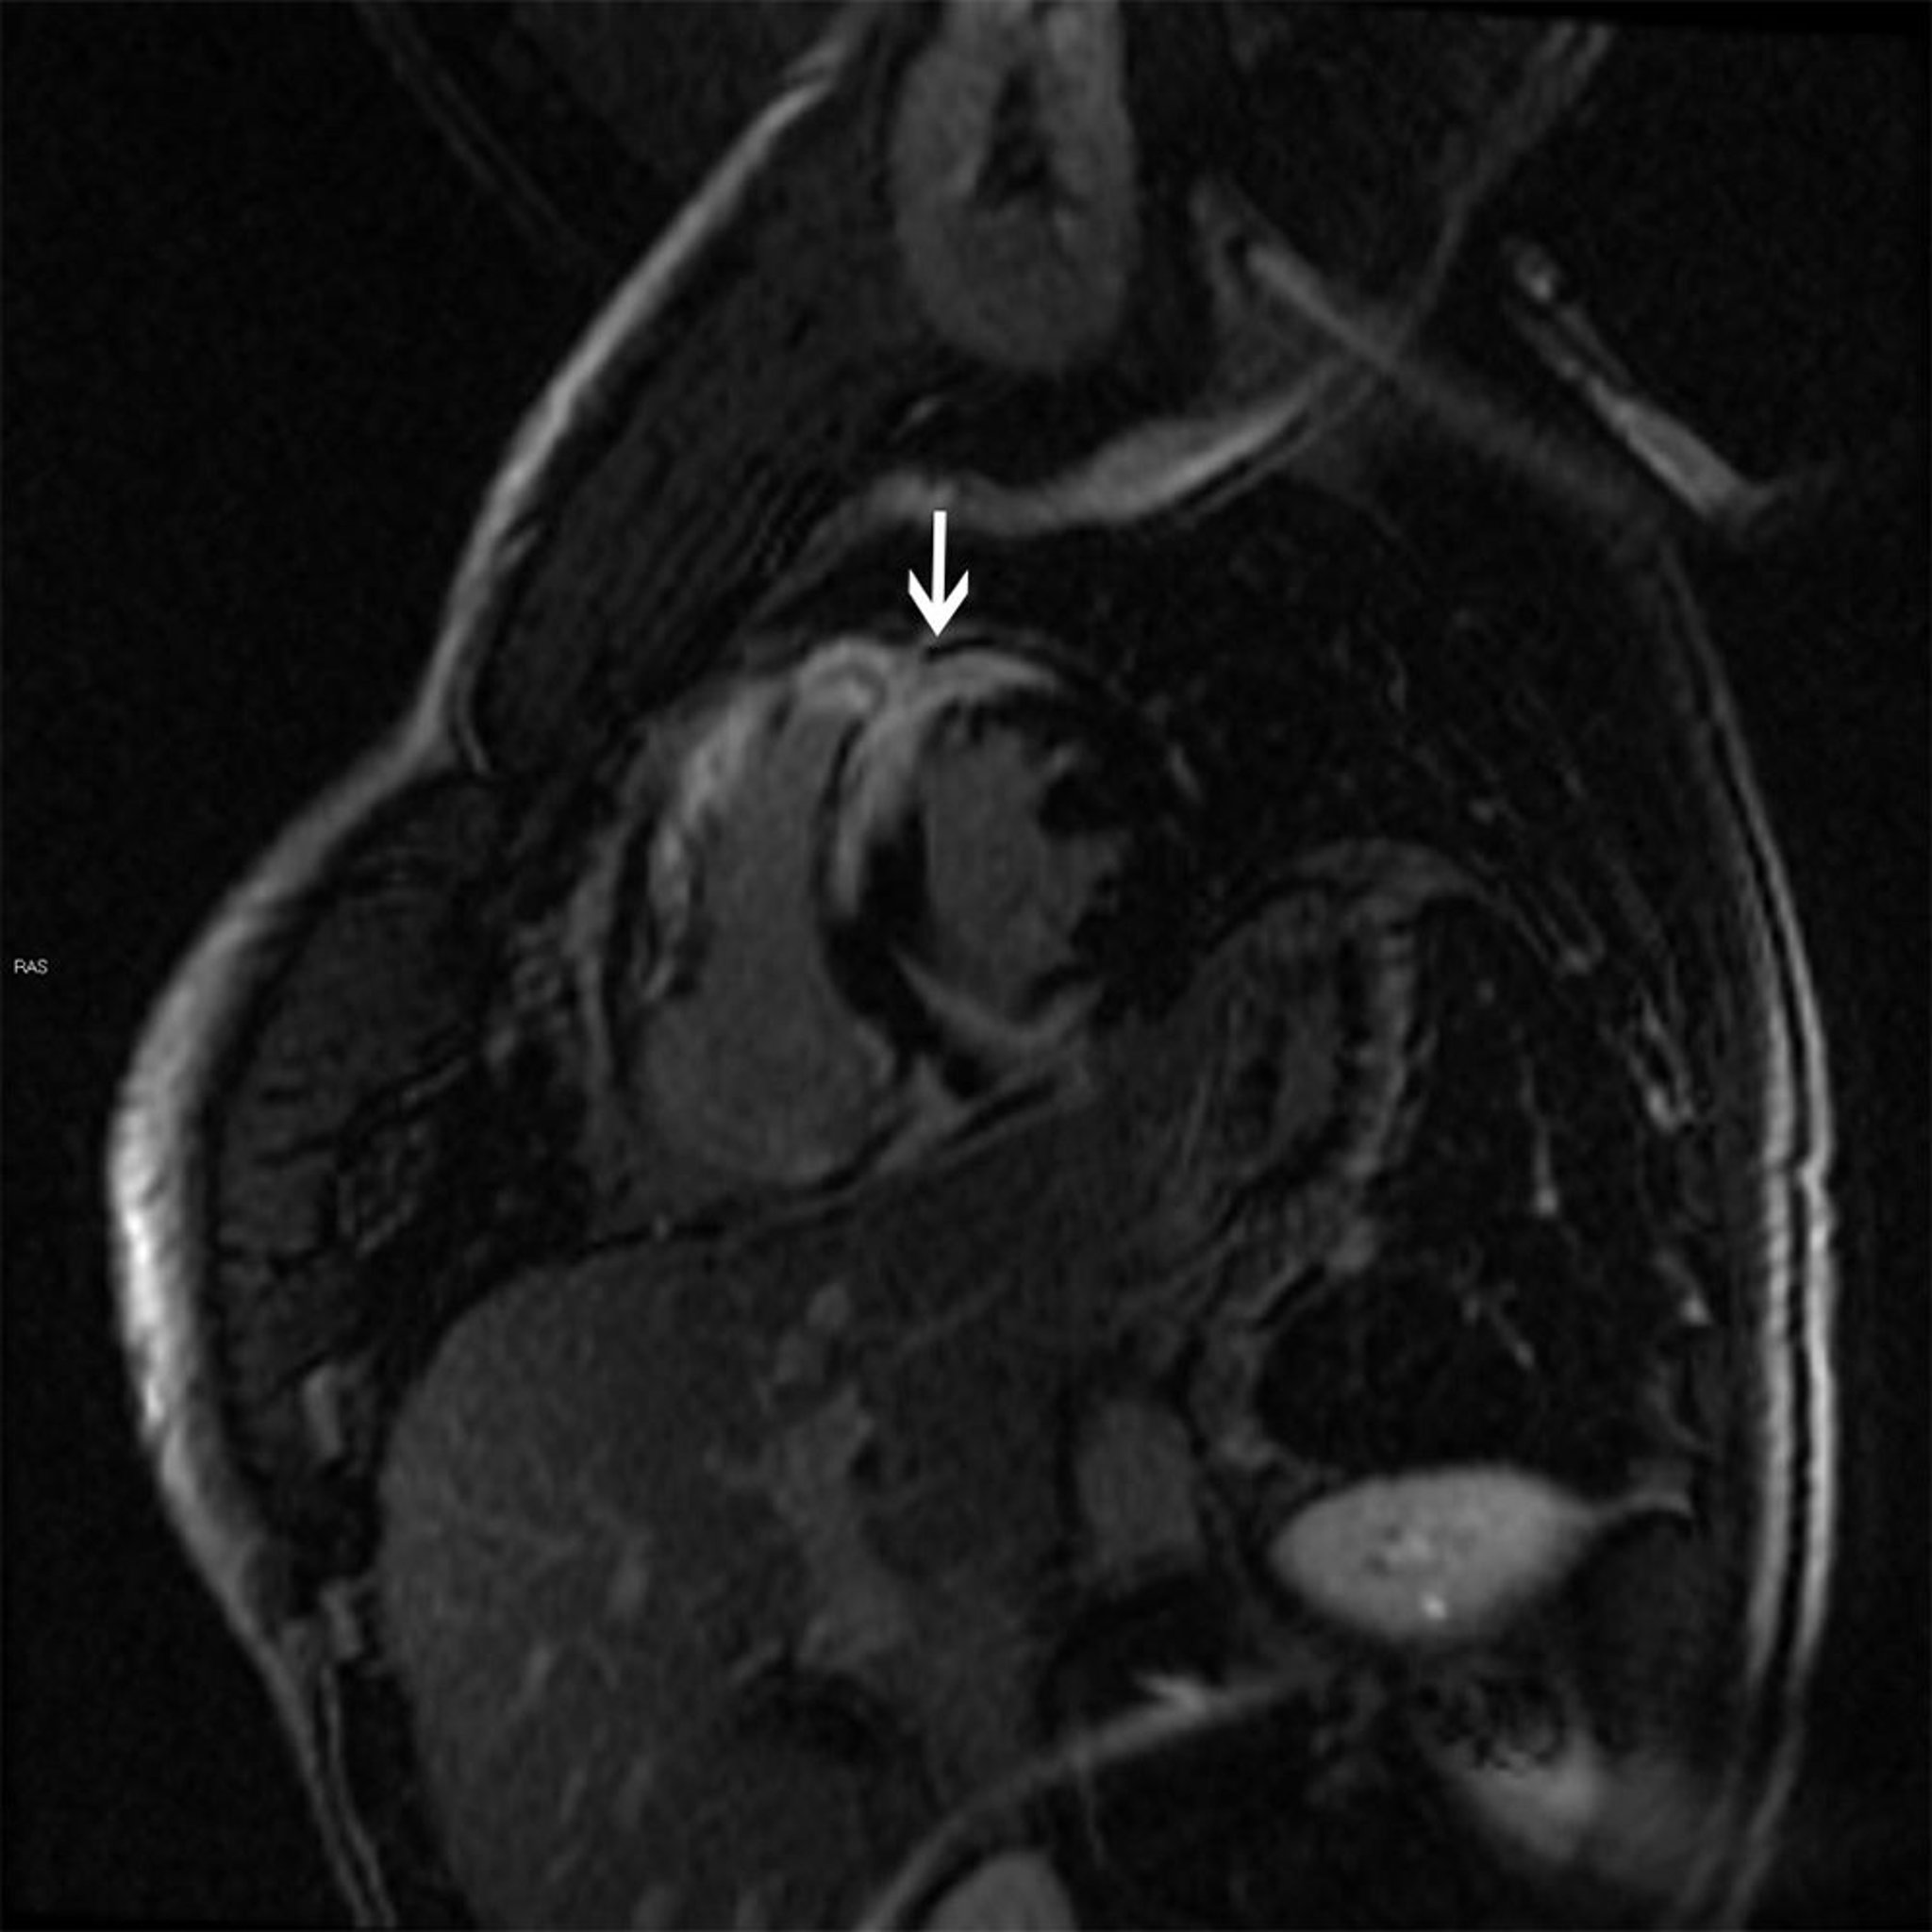

心臓サルコイドーシスのMRI所見

この心臓MRI画像には,サルコイドーシスの特徴である,ガドリニウムによる斑状の遅延造影像(矢印)が認められ,サルコイドーシスは拡張型または肥大型心筋症を引き起こすことがある。